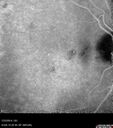

Macroaneurysm - Resolved without treatment416 views87 year old female with vision loss OD. Initial FA showed no leakage so no treatment was done and the fluid absorbed over 4 months. Initial VA 20/100, Final VA 20/80

Macroaneurysm - Resolved without treatment402 views87 year old female with vision loss OD. Initial FA showed no leakage so no treatment was done and the fluid absorbed over 4 months. Initial VA 20/100, Final VA 20/80

Macroaneurysm - Resolved without treatment400 views87 year old female with vision loss OD. Initial FA showed no leakage so no treatment was done and the fluid absorbed over 4 months. Initial VA 20/100, Final VA 20/80

Macroaneurysm - Resolved without treatment391 views87 year old female with vision loss OD. Initial FA showed no leakage so no treatment was done and the fluid absorbed over 4 months. Initial VA 20/100, Final VA 20/80

Macroaneurysm - Resolved without treatment390 views87 year old female with vision loss OD. Initial FA showed no leakage so no treatment was done and the fluid absorbed over 4 months. Initial VA 20/100, Final VA 20/80

Macroaneurysm - Resolved without treatment387 views87 year old female with vision loss OD. Initial FA showed no leakage so no treatment was done and the fluid absorbed over 4 months. Initial VA 20/100, Final VA 20/80

Macroaneurysm - Resolved without treatment380 views87 year old female with vision loss OD. Initial FA showed no leakage so no treatment was done and the fluid absorbed over 4 months. Initial VA 20/100, Final VA 20/80

Macroaneurysm - Resolved without treatment374 views87 year old female with vision loss OD. Initial FA showed no leakage so no treatment was done and the fluid absorbed over 4 months. Initial VA 20/100, Final VA 20/80

Macroaneurysm - Resolved without treatment371 views87 year old female with vision loss OD. Initial FA showed no leakage so no treatment was done and the fluid absorbed over 4 months. Initial VA 20/100, Final VA 20/80

Macroaneurysm - Resolved without treatment369 views87 year old female with vision loss OD. Initial FA showed no leakage so no treatment was done and the fluid absorbed over 4 months. Initial VA 20/100, Final VA 20/80

Macroaneurysm - Resolved without treatment367 views87 year old female with vision loss OD. Initial FA showed no leakage so no treatment was done and the fluid absorbed over 4 months. Initial VA 20/100, Final VA 20/80

Macroaneurysm - Resolved without treatment362 views87 year old female with vision loss OD. Initial FA showed no leakage so no treatment was done and the fluid absorbed over 4 months. Initial VA 20/100, Final VA 20/80

Macroaneurysm - Resolved without treatment361 views87 year old female with vision loss OD. Initial FA showed no leakage so no treatment was done and the fluid absorbed over 4 months. Initial VA 20/100, Final VA 20/80

Macroaneurysm - Resolved without treatment358 views87 year old female with vision loss OD. Initial FA showed no leakage so no treatment was done and the fluid absorbed over 4 months. Initial VA 20/100, Final VA 20/80

Macroaneurysm - Resolved without treatment357 views87 year old female with vision loss OD. Initial FA showed no leakage so no treatment was done and the fluid absorbed over 4 months. Initial VA 20/100, Final VA 20/80

Macroaneurysm - Resolved without treatment355 views87 year old female with vision loss OD. Initial FA showed no leakage so no treatment was done and the fluid absorbed over 4 months. Initial VA 20/100, Final VA 20/80

Macroaneurysm - Resolved without treatment353 views87 year old female with vision loss OD. Initial FA showed no leakage so no treatment was done and the fluid absorbed over 4 months. Initial VA 20/100, Final VA 20/80

Macroaneurysm - Resolved without treatment349 views87 year old female with vision loss OD. Initial FA showed no leakage so no treatment was done and the fluid absorbed over 4 months. Initial VA 20/100, Final VA 20/80